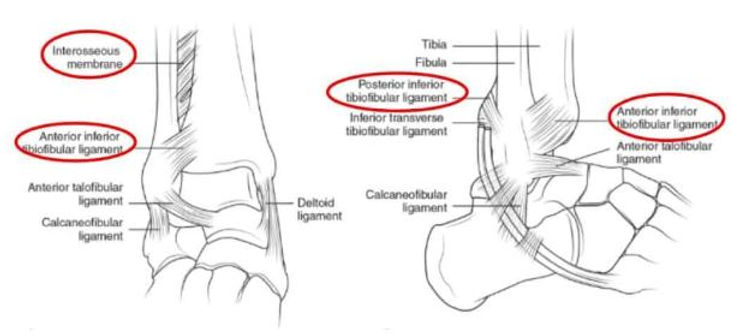

what are the ligaments of the tibiofibular joint?

anterior inferior tibiofibular (AITF)

posterior inferior tibiofibular (PITF)

what are the lateral ligaments of the talocrural joint?

anterior talofibular (ATF)

posterior talofibular (PTF)

calcaneofibular (CF)

which ligament of the talocrural joint will be the 1st to be injured in an ankle sprain?

anterior talofibular (ATF)

which ligament of the talocrural joint will be 2nd to be injured in an ankle sprain?

calcaneofibular (CF)